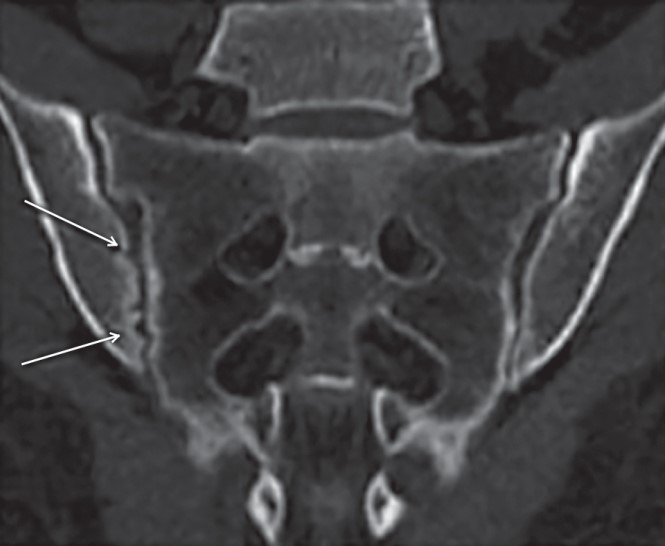

Лікарі, ті маги білих халатів, бачать сакроілеїт через рентген чи МРТ. Не ду́мають два рази. Але іноді цього замало. Хто точно скаже? Правильно, справжній спеціаліст з суглобами. Навіть якщо ти не віриш у медицину, довірся. Правда на їхньому боці.